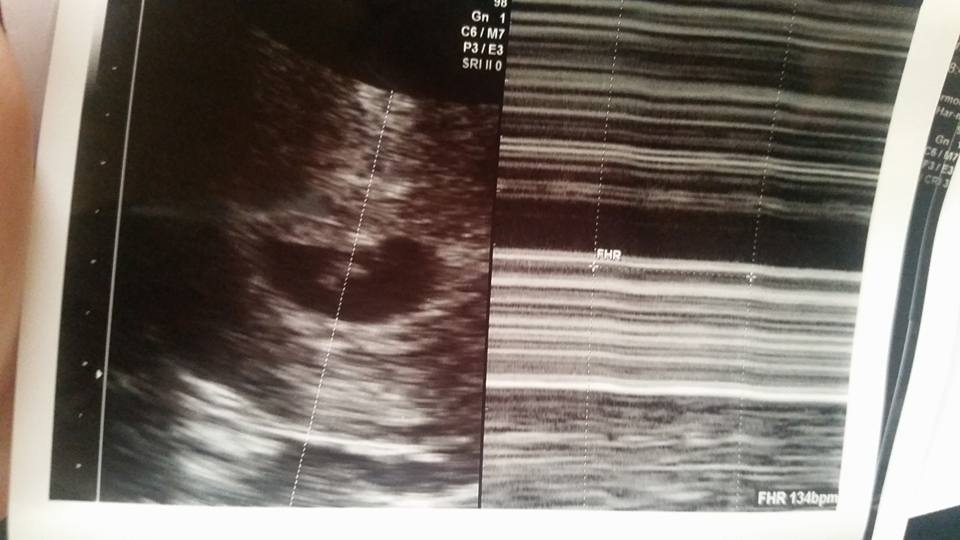

according to my last period I should be 7w1d but tech said I'm measuring 6w4d Heartrate was 134! I go back in two weeks for regular ultrasound and hopefully we'll get to hear the heartbeat, plus DH will be there too so I'm excited!